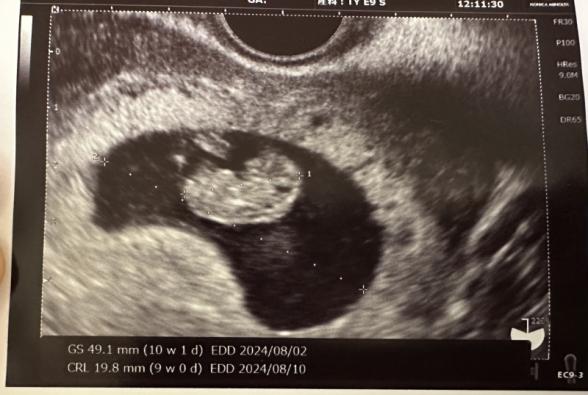

9週2日です。

1月6日に検診に行き心拍確認が出来ました。

赤ちゃんは心拍もあり、子宮の中の出血では無く、外側の出血で、内診の影響や膣剤を入れたからかな?と言われました。